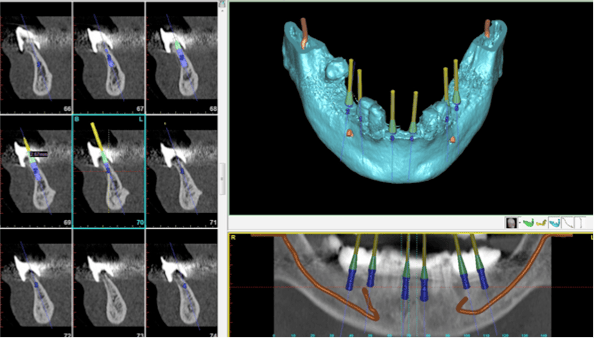

One of the challenges to a full mouth dental implant-supported prostheis is the transition from a partially dentate state to a fully edentulous state. Many patients are unable to manage a complete denture, especially for the lower jaw. To avoid the inconvenience of having to adapt to a set of full dentures in the interim period, we decided to go with immediate loading of the implants with a fixed temporary prosthesis. This was done using CT-guided dental implant surgery. First, a radio-opaque scan prostheses were made and CT scans were taken and the data were entered into Simplant Planner, a dental implant treatment planning software. Based on the ideal setup of teeth in the scan prostheses, implants were placed in the model generated in the software. The plan was uploaded to the Simplant facility in Belgium.

Based on the plan, a surgical guide was made by stereolithography. The purpose of the guide was to ensure that the implants would be placed in exactly the positions as planned. The guides were then couriered back to a Singapore laboratory for fabrication of provisional prostheses that would be fitted onto the implant on the day of implant surgery. On the day of surgery, the guides were fitted over the existing teeth and implants placed in accordance to the guide. Once the implants were inserted, all the remaining teeth were extracted and the prostheses fitted onto the implants.